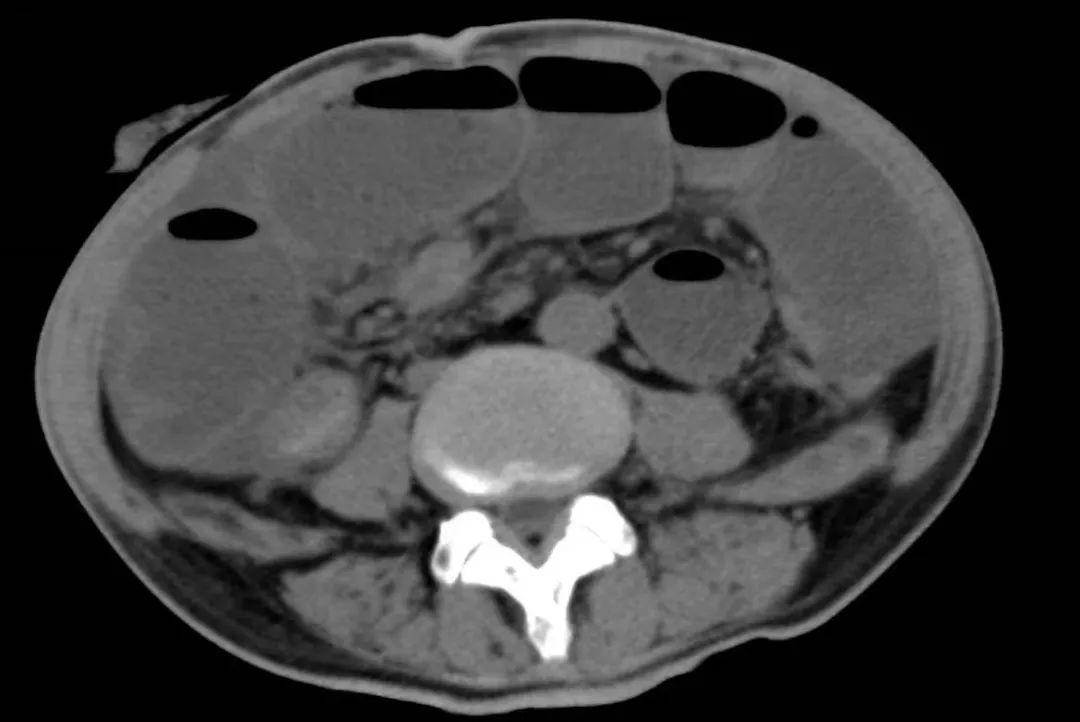

2022年5月的一个凌晨,一位93岁的老奶奶因为腹胀和呕吐被送到了新龙泽院区急诊科,经过问诊和初步查体后,接诊医生考虑患者存在肠梗阻,立即为患者申请了急诊腹部CT检查,结果显示患者的升结肠存在一个巨大的肿物堵塞了肠腔。在给予补液和胃肠减压的同时,普外科立即对患者的病情进行了紧急评估和讨论。肿瘤导致患者出现肠梗阻,手术是唯一的解决方案,但患者高龄且身体非常瘦弱,围手术期发生肺部感染、心脑血管事件等并发症的概率非常高。普外科高鹏骥主任医师制定了急诊实施腹腔镜下右半结肠切除的手术方案,并在麻醉科和手术室医护团队的密切配合下顺利完成了手术。